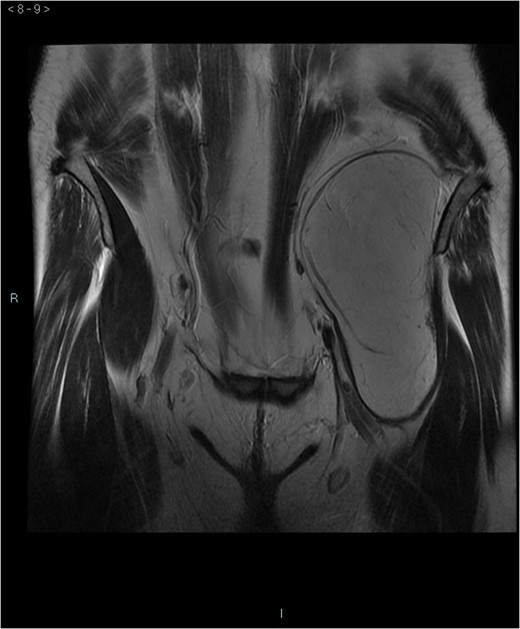

A 58-year-old woman was evaluated for lower abdominal pain, without additional symptoms. An abdominal ultrasonography revealed the presence of a 15 cm homogenous mass, located in the left pelvic cavity. Subsequent MRI showed a capsulated mass, isointense with the adipose tissue, longitudinally extending from the left inguinal area to the left leg root and located on the medial aspect of the left iliac bone. MRI also revealed within the mass some fibrotic branches containing small blood vessels. No evidence of extracapsular invasion of the surrounding structures was evident (Figs 1–6).

Preoperative differential diagnosis is mainly based on radiologic imaging and is very difficult, because no pathognomonic signs exists for diagnosis of hibernoma; usually CT-scan shows an homogenous lesion, whose density is between subcutaneous fat and skeletal muscle; MRI shows slightly lower signal intensity on T1 weighted spin-echo (T1WSE), marked enhancement and partial fat suppression on short Tau inversion recovery (STIR) and fat-saturated sequences [5].